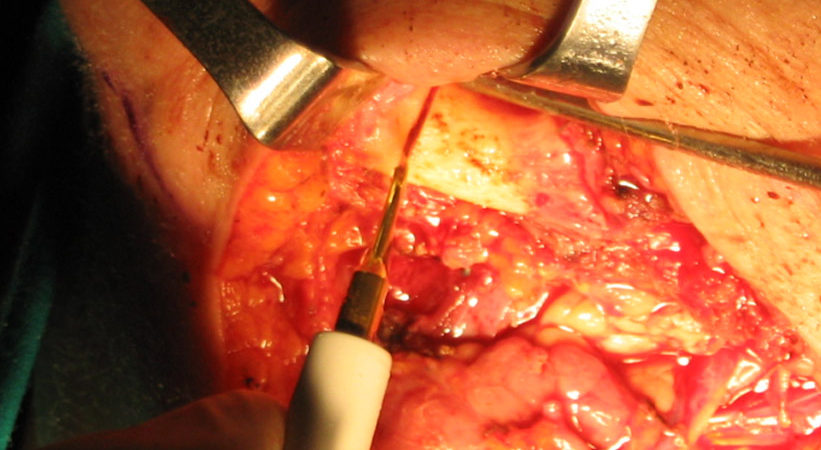

Donna di 76 anni portatrice di un carcinoma squamoso del trigono retromolare infiltrante l’osso mandibolare T4N0.

La paziente è stata sottoposta ad intervento “commando”.